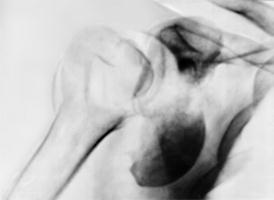

Рис. 1. Рентгенограмма плечевого сустава (прямая проекция) при переломовывихе правого плеча: фрагмент суставной поверхности головки плечевой кости находится вне суставной впадины у ее передненижнето отдела.